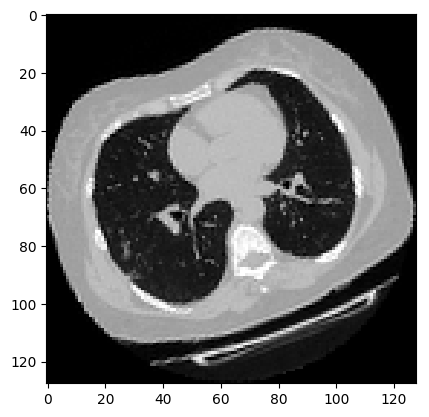

可视化增强型 CT 扫描。

images, labels = train_dataset.__getitem__(0)

print(images.shape)

image = np.squeeze(images, 3)

print("Dimension of the CT scan is:", image.shape)

plt.imshow(np.squeeze(image[:, :, 30]), cmap="gray")

plt.show()